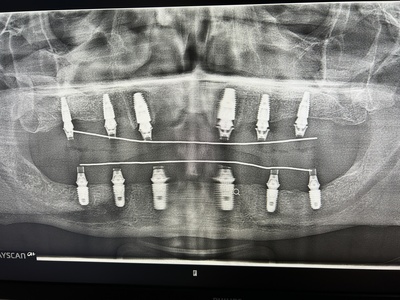

Боюсь только стоматологов. С зубами беда(плохая наследственность и психологическая травма из детства) сделали своё дело: много зубов раскрошились и сгнили, остались торчать осколки. Страх заставлял меня переживать зубную боль обпиваясь таблетками, когда совсем было плохо.

Сегодня иду на удаление 4ки. Страшно до жути, и неохота выслушивать нравоучения от врачей, но всё равно пойду.